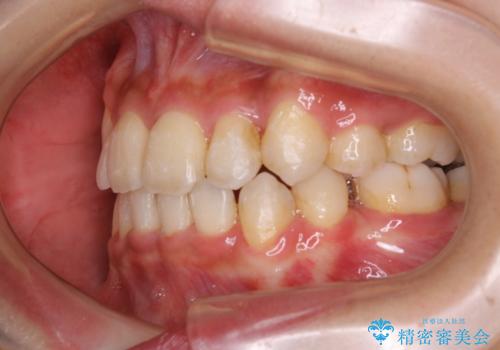

- 元々は海外でワイヤー矯正を行っていたが、コロナ禍で海外への往来が難しくなり、治療を中断せざるを得なくなってしまった方です。

ご本人のご希望により、インビザラインによる治療を行いました。

ブラケット除去直後に目立っていた下顎前歯部の大きなブラックトライアングルもあまり目立たなくなり、大変喜んでいただけました。